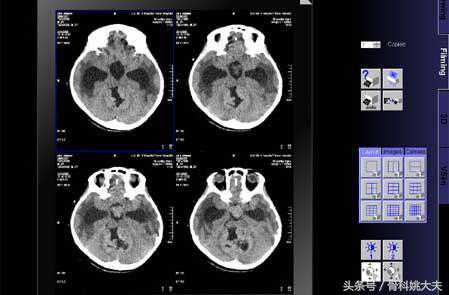

脑、脊髓:脑梗看核磁,出血看CT,其余包括脑肿瘤大多核磁最佳;

CT是用x射线束对人体检查部位一定厚度的层而进行扫描。由探测器接收透过该层面的X射线,转变为可见光后,由光电转换器转变为电信号,再经模拟数字转换器转为数字.输入计算机处理从而获得数字化的重建断层图像.其密度分辨力明显优于x射线图像,扩大了人体的检查范围,提高了病变的检出率和诊断的准确率。前面已经谈过,人体不同组织结构密度不同.对x射线的吸收程度也不风同,这点与x光片颇为相似*CT片上的黑影也表示低吸收区,即低密度区.如肺部;白影则表示高吸收区,即高密度区,如骨骼。但CT的密度分辨力要远高于x射线图像、这就是它的突出优点。它能够使软组织这种密度差别小,吸收系数接近于水的结构也形成对比而成像,不论是那些由软组织构成的器官,如脑、脊髓、纵隔、肺、肝、胆、胰以及盆部器官等,还是其病变都可清晰显示。CT的另一大突破就是使所谓的高密度和低密度有了量的概念,用CT值来说明密度高低.这是x射线图像无法做到的。另外,CT图像是断层图像.通常是横断面.所以为了显示整个器官,就需要多帧连续的断层图像,这也就是为什么一张CT片上有若干个小图像的原因。CT设备比较昂贵,检查费用较高.某些部位的检查、诊断价值,尤其是定性诊断,还有一定限度,所以除颅脑、肝、胆、胰、脾等脏器疾病外,不宜将CT检查视为常规诊断手段。

我们已经知道,不同组织的密度差异是CT成像的基础.并有CT值表示密度的高低。但MR成像却有多个参数,如T1、T2和自旋质子密度等。Tl是纵向弛豫时间.T2是横向弛豫时间.它们的具体内容我们不必过多了解,只要知道不同组织结构其T1、T2和质子密度不同。例如,正常肝的T1值是140-70,肝癌则为300-450;又如.正常大脑的T1值是600.T2值是100;正常小脑T1值是585,T2值是90。有了这种差异,我们就可以获得选定层面各种正常或病理组织的影像。与CT一样,MR图像也是以不同灰度显示的黑白影像.但CT只反映组织密度,而MR图像则可反映T1、T2或质子密度。在T1图像上,脂肪呈白影;脑与肌肉影像灰;骨与空气影像黑暗。需要注意的是,由于T1和T2反映的是不同时间,所以在T1和T2图像上,相同组织的灰度可能不同,甚至相反。例如,脑脊液在Tl图像上影像黑(低信号),而在T2图像上呈白色(高信号)。不同病理组织的信号强度也不相同.例如,水肿在Tl图像上呈黑影,而在T2图像上呈白影;钙化灶则在T1和T2图像上均呈黑影。